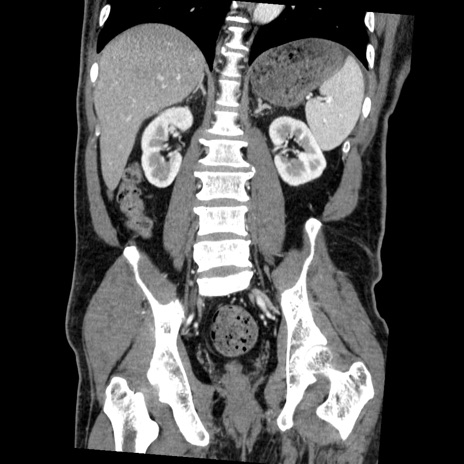

症例22(冠状断像)

【症例】50歳代男性

【主訴】腹痛

【現病歴】AVMからの被殻出血のため回復期リハ病棟入院中。 本日午後3時頃急に下腹部痛が出現した。

【既往歴】AVM、被殻出血、虫垂炎、高血圧

【身体所見】意識晴明、左半身不全麻痺、会話の理解は良好、36.5°C、腹部:膨隆、全体に板状硬、下腹部正中に圧痛点あり、反跳痛-、筋性防御不明、右下腹部にope scar

【データ】WBC 9400、CRP 0.06